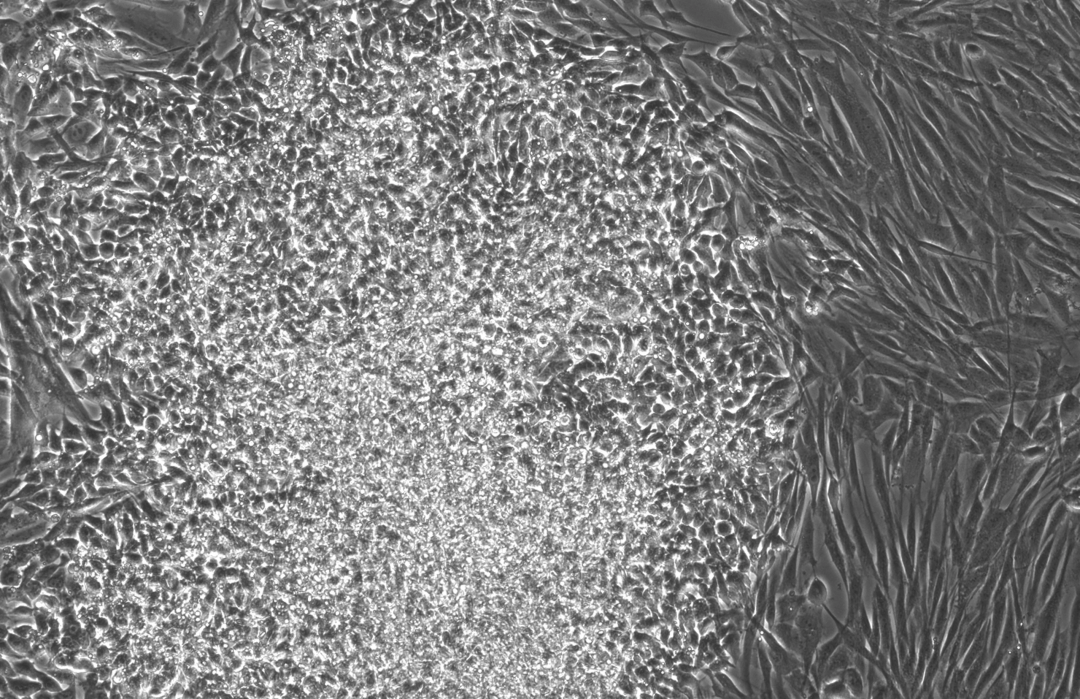

下面这三张图展示的是,OpenAI设计的蛋白质能更高效地诱导干细胞重编程:

使用RetroSOX与RetroKLF变体(结合OCT4, MYC)重编程10天后,出现了大量具有紧凑、圆形形态的集落,这是细胞迈向iPSC状态的典型特征

在三次独立的实验中,成纤维细胞的早期(SSEA-4)和晚期(TRA-1-60, NANOG)标记物水平均出现急剧上升,且晚期标记物的出现时间比使用野生型OSKM组合方案提前了数天。

在第10天,使用不同RetroSOX和RetroKLF变体组合(RK1-RK4)的细胞,其晚期标记物TRA-1-60(左)和NANOG(右)的表达水平远高于使用标准OSKM(检测不到)的对照组